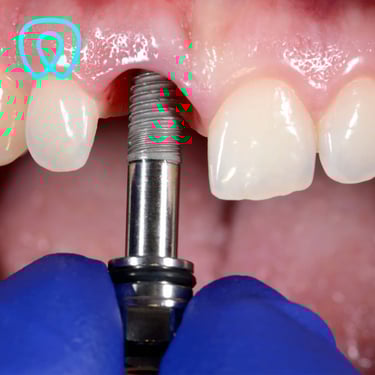

Contamos con todas las especialidades dentales: ortodoncia, implantes, cirugía, endodoncia, periodoncia, odontopediatría, odontología cosmética, prótesis dental.

Servicios Dentales

Atención integral en odontología para todas las edades y especialidades con enfoque en la prevención.